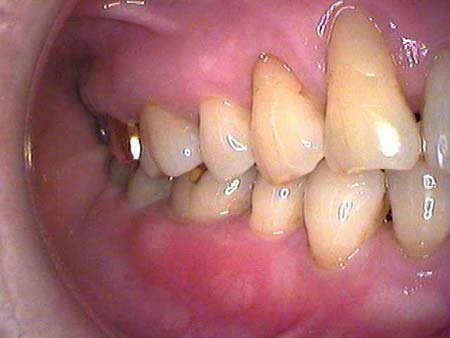

| ● | 4月に行って白内障で、糖が出ていてしばらく出来ないって言われて。それにこの頃後頭部の頭痛がひどいって言ってたんですね。物が歯につまりやすいっておっしゃって、見たら歯ぐきが腫れてきていて……。でもすごいですね6ミリ近くあったポケットも歯石取りをしたらすぐ4ミリまで下がったんですね。 |

| ● | 変化はあるけど、糖尿病があって、しかもこのように維持しているなんて凄いんですよ。 定期検診はほんときちんと来て歯石取りもしていらっしゃっているし、歯間ブラシまできちんとしてますよね。 詰めている所が悪くなって再治療もしていますが、それもきちんと受けてますね。 それにしても全部の歯がこのようにしっかりとしている事はすばらしいですよ。 |